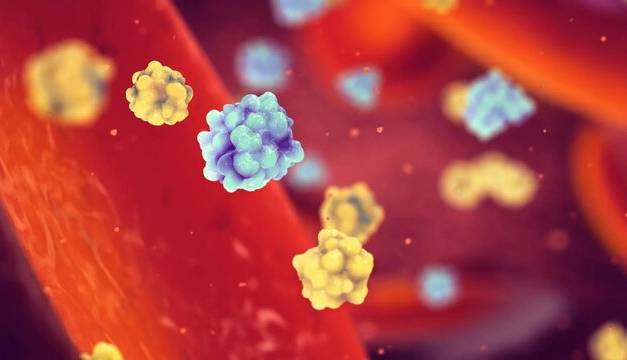

این ادویه تا حدی از سرطان جلوگیری می کند!